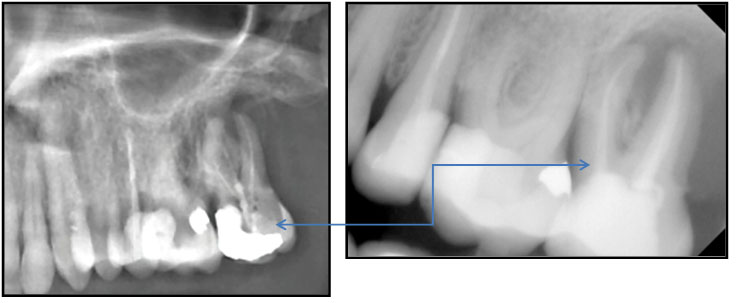

Ατελής ενδοδοντική θεραπεία που οδήγησε σε περιακρορριζική καταστροφή.

Η επανάληψη της ενδοδοντικής θεραπείας δεν οδήγησε σε πλήρη επούλωση της βλάβης,

καθώς είναι αναγκαία και η περιοδοντική θεραπεία του δοντιού.